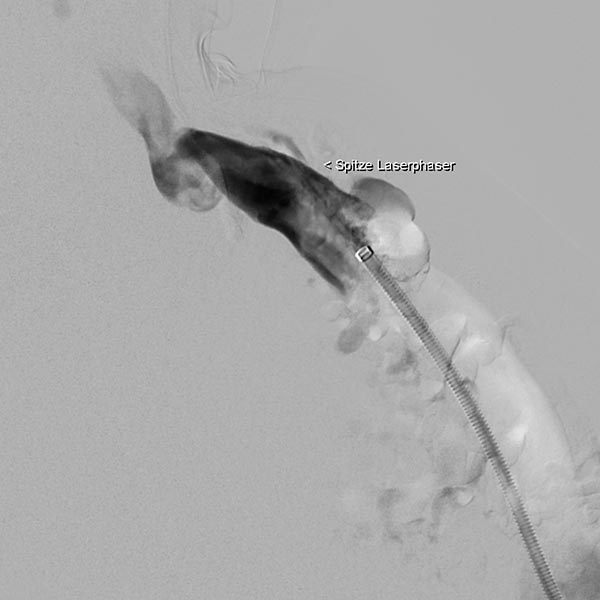

Durch diese Schleuse wird eine Laserfaser zur endovaskulären Lasertherapie vorgeführt. Durch die Erhitzung des Laserstrahls kommt es zu einer massiven Reizung der Venenwand, die sich anschließend sehr schnell verschließt. Um die Laserspitze kommt es sofort zur Thrombusbildung (weiß, da als Kontrastmittelaussparung sichtbar).

Nach Verschluss durch die Laserfaser und Anspritzen über die zurückgezogene Schleuse kommt es nicht mehr zu einem Abstrom des Kontrastmittels über die Kommunikationsvene, die erfolgreich verschlossen ist. Es kontrastiert sich nur noch die venöse Malformation. Diese ist jetzt bereit zur Sklerosierungsbehandlung, da dieses nicht mehr abfließen kann.